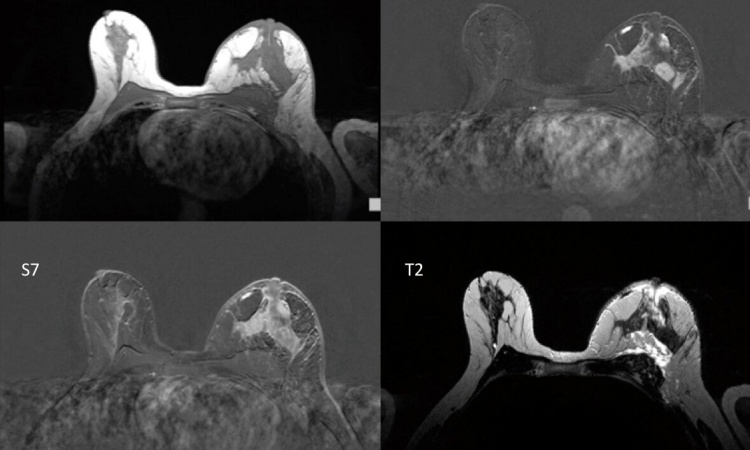

On conventional MR images lightness and darkness don’t correspond with absolute values but merely serve to help the radiologist make a diagnosis based on the respective contrasts. Modern MRI procedures, such as MR fingerprinting, however, can precisely quantify the three basic MRI parameters (T1 relaxation timings, T2 relaxation timings and proton density). This data can be used to generate maps which, at first glance, look like conventional contrast images, but which are capable of far more: they contain accurate measurements. Each pixel of a T1 map for instance corresponds with an exact T1 measurement. ‘This way the differences between pathological and healthy tissue can be clearly established. When monitoring the progress of treatment, for instance, it is possible to see how the measurements change, and to assess the efficiency of the treatment,’ Trattnig explains.

Until recently, the generation of a T1 or T2 map took about 10 to 15 minutes – too long for clinical routine applications. The new technologies make T1 or T2 mapping possible in one to two minutes. Furthermore, there is now the respective software that evaluates the maps at high speed. ‘This makes it really interesting for clinical routine,’ he points out. As the maps always contain the entire MRI information the conventional contrast images can be synthetically generated retrospectively. ‘There is no need to examine the patient with different sequences. A one-off measurement of the T1 and T2 values suffices,’ Trattnig explains.